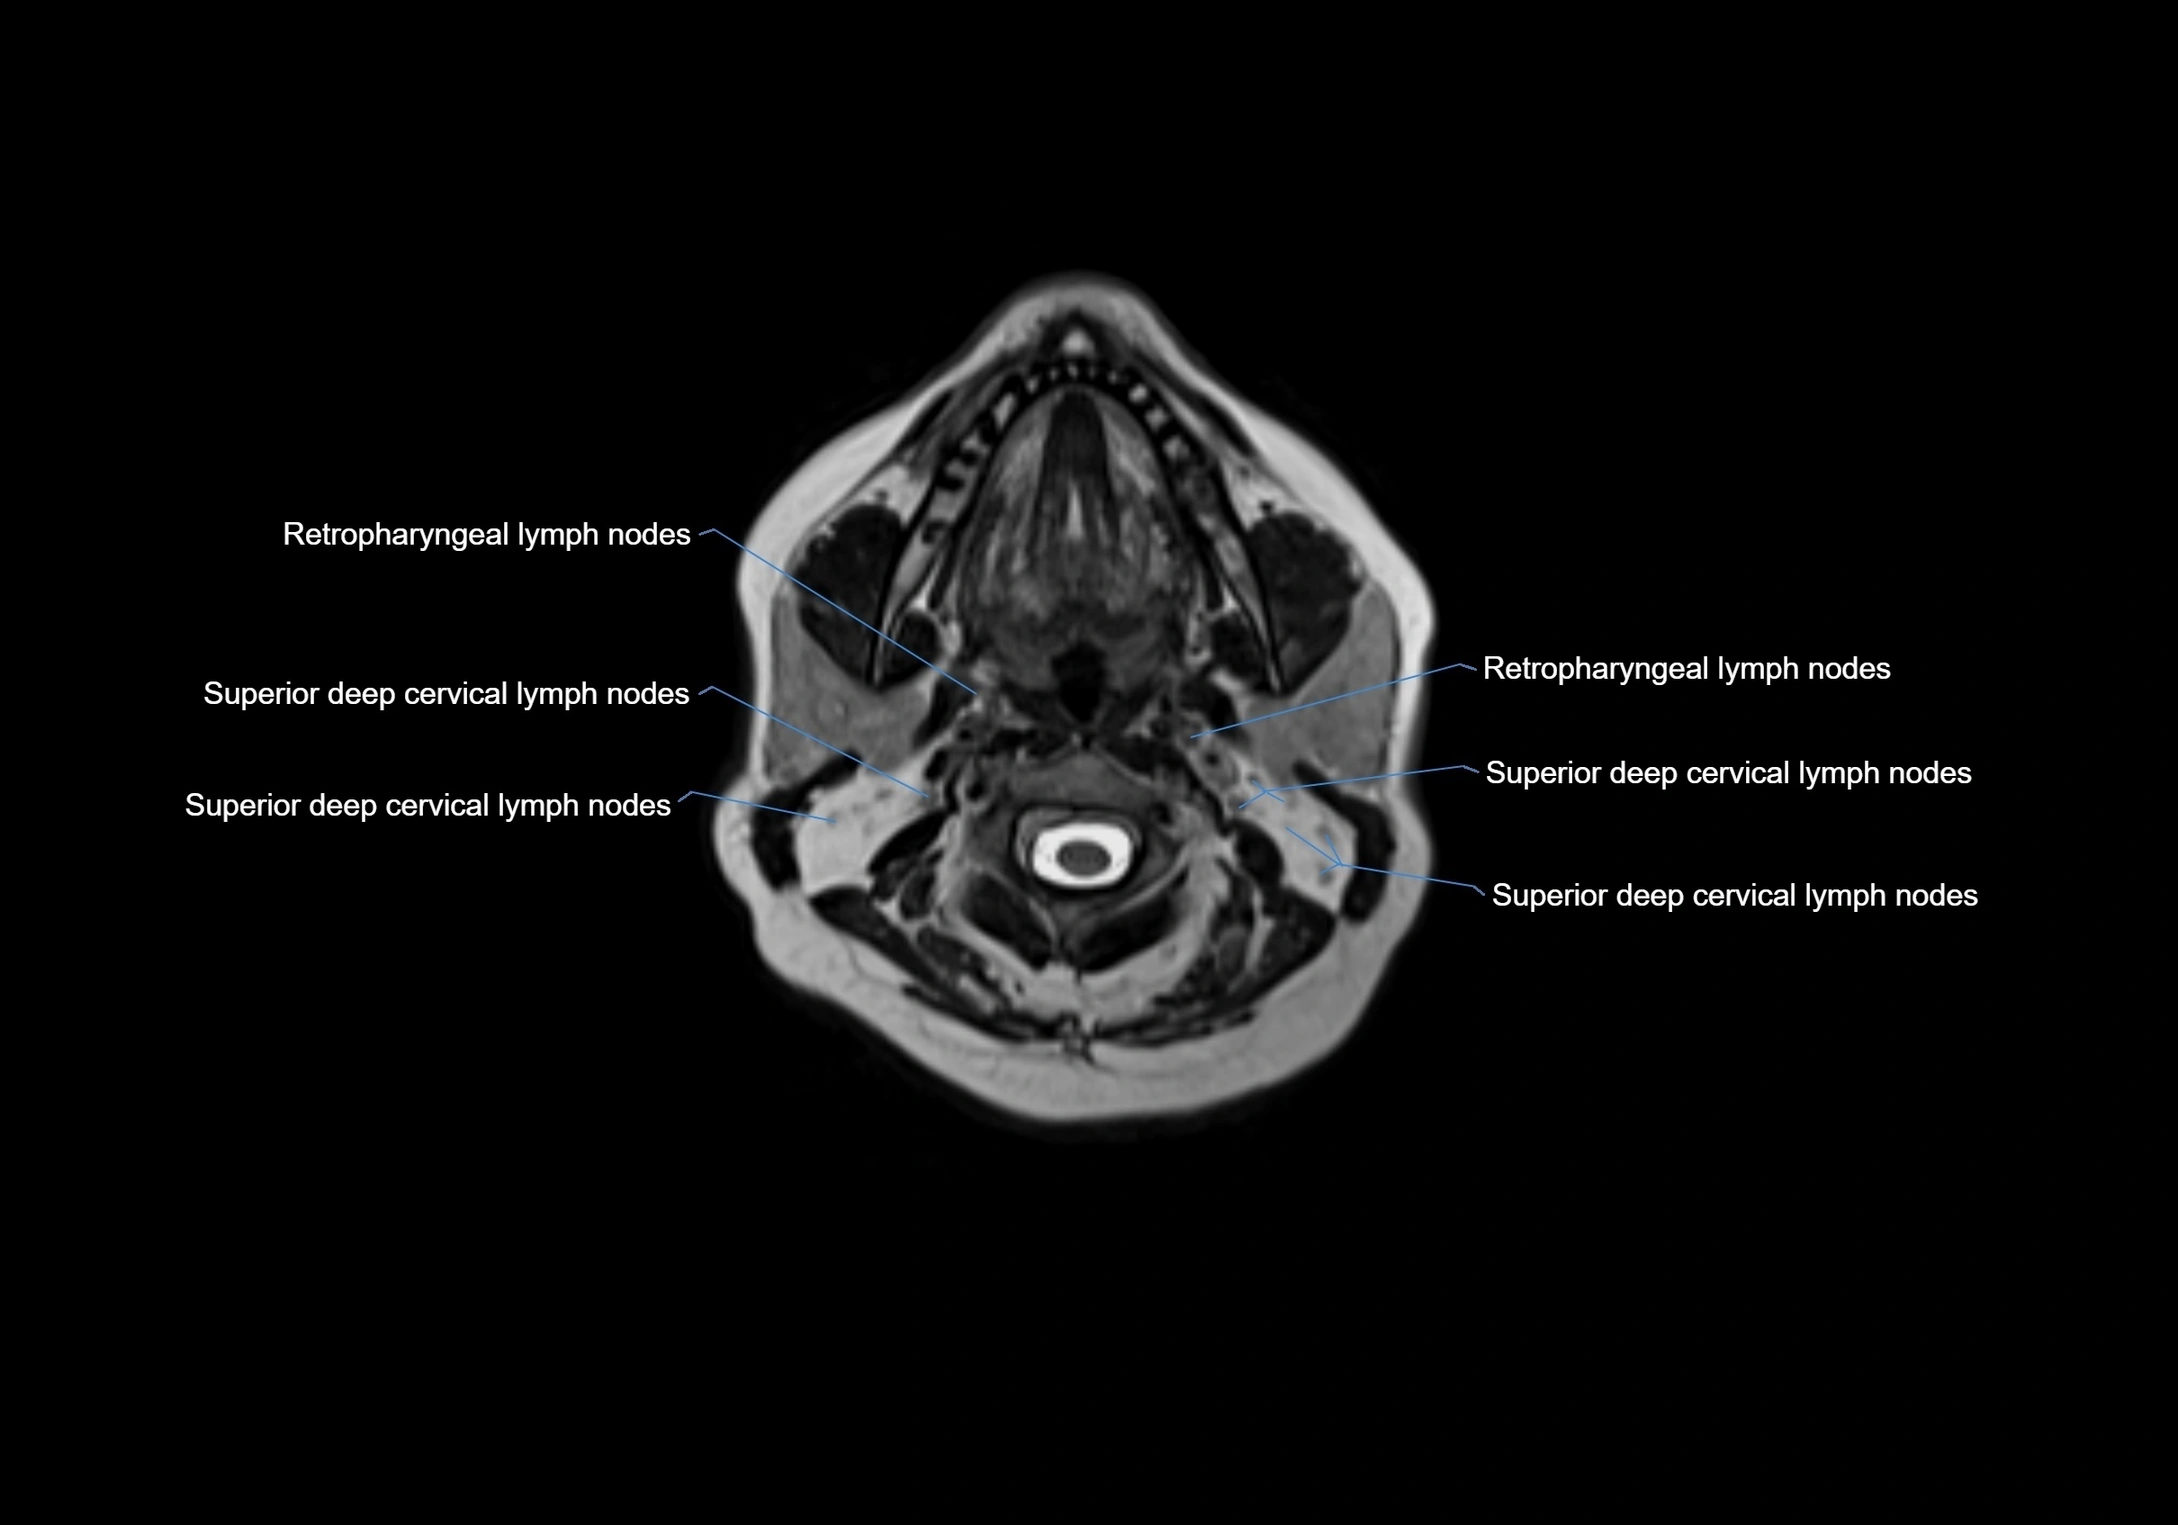

Accessory lymph nodes

Accessory lymph nodes are small, secondary lymph nodes located along the main facial and cervical lymphatic chains, often adjacent to primary lymph nodes, such as preauricular, submandibular, or occipital nodes. They are typically less than 5 mm in diameter, embedded within subcutaneous fat or connective tissue, and may be variable in number and location. These nodes provide additional filtration and immune surveillance for lymph collected from the face, scalp, and neck regions. Accessory lymph nodes are usually non-palpable in healthy individuals but may enlarge in response to infection, inflammation, or metastasis, making them clinically significant.

Location

• Found along primary lymph node chains, including preauricular, submandibular, parotid, and occipital regions

• Embedded in subcutaneous fat or superficial fascia, often lateral or posterior to primary nodes

• Variable in number; may occur unilaterally or bilaterally, depending on individual anatomy

MRI images

image